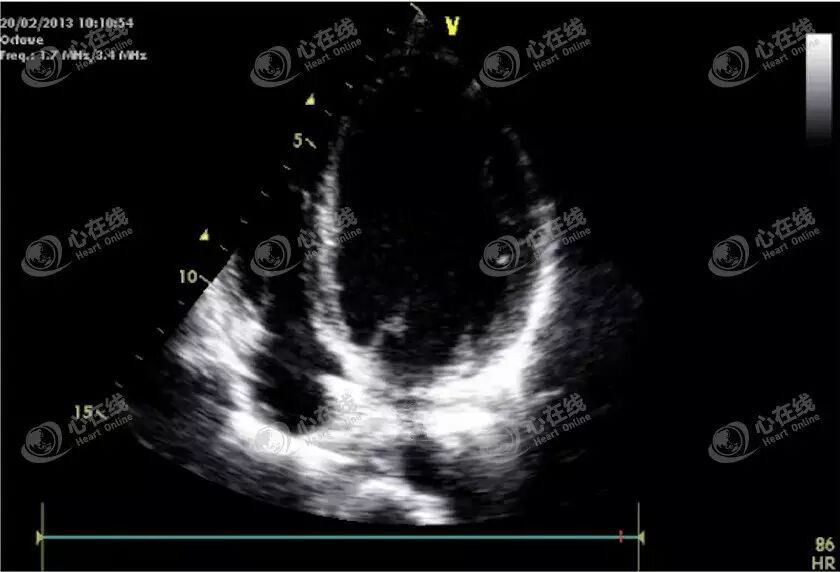

(1)肥厚型心肌病

观察图A可见室壁、室间隔厚度均明显增加,提示肥厚型心肌病。观察图B可见绿色箭头处室壁运动明显减弱,由冠心病、心肌梗死所致,我们称之为节段性的室壁运动异常。